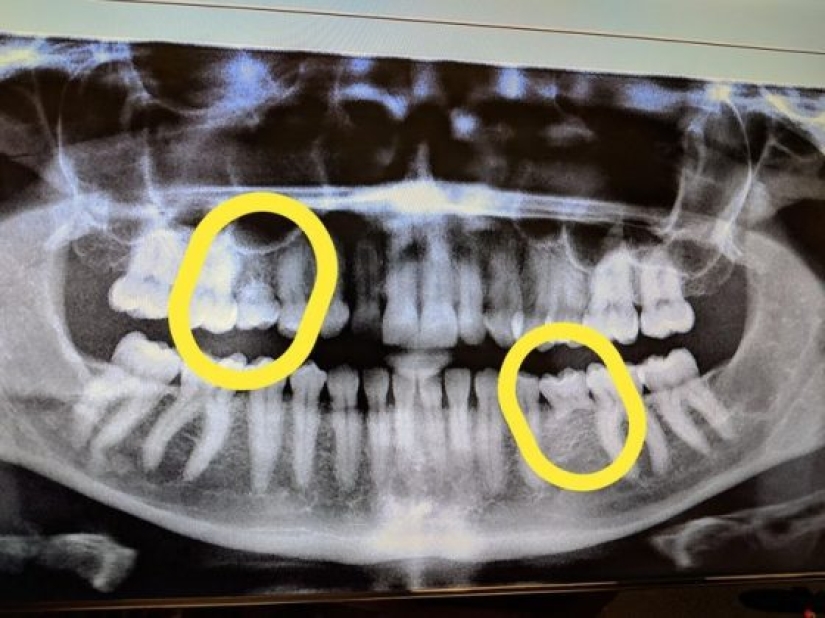

11. “At the moment the tooth fairy owes me a lot of money. I am 33 years old and here are my x-rays showing my remaining baby teeth.”